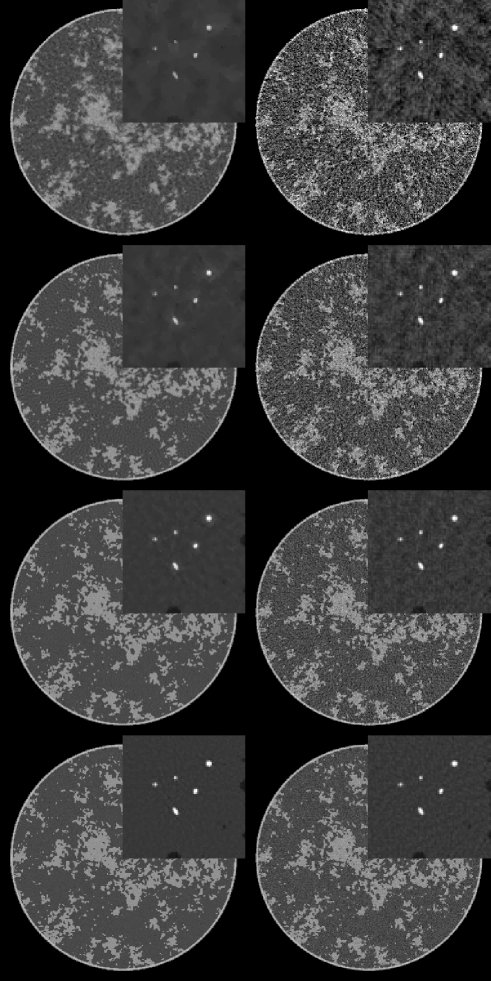

For this initial survey of a breast CT simulation, we show two main sets of results. The first set of images are reconstructed from noiseless data for different numbers of views. The idea is to see how well TV-minimization performs in recovering the complex breast phantom under ideal conditions. The second set of images includes noise at a fixed exposure, and as described in Sec. II-B, the noise-level per projection increases with the the number of projections.

IV-A image reconstruction from noiseless data

In Fig. 2, we show images reconstructed from 64 to 512 projections for both TV-minimization and filtered back-projection (FBP). For TV-minimization in this study we set , which corresponds to a very tight data constraint. As noted above the sparsity of the gradient magnitude is on the order of 50,000. Accordingly, from CS-based arguments, one could only expect to start to achieve accurate reconstruction when the number of measured line integrals exceeds 100,000, which in this case means 100 projections. An important part of CS theory deals with computing the factor between the sparsity level and necessary number of measurements for accurate recovery. This factor is unknown for TV-minimization applied to the X-ray transform, but we can see from the reconstructions that the accuracy is greatly improved in going from 128 views to 256 views. There is still a perceptible improvement in the image recovery in going to 512 views, which still represents an under-determined system despite the fact that 512 views is normally not thought of as a sparse-view data set. Again, it is the complexity of the phantom which is responsible for this behavior. The accompanying FBP results give an indication on the ill-posedness of reconstruction from the various configurations with different numbers of projections.

The results for the micro-calcification ROI are interesting in that this particular feature of the image is recovered for all data sets down to the 64-projection data set. This is not too surprising because the micro-calcifications are certainly sparse in the gradient magnitude. But this result emphasizes that the success of an image reconstruction algorithm depends also on the imaging task and the subject.

For the larger goal of determining the optimal number of views, it is clear that ”structure noise” – artifacts due to the complex object function– can play a significant role for this breast phantom.